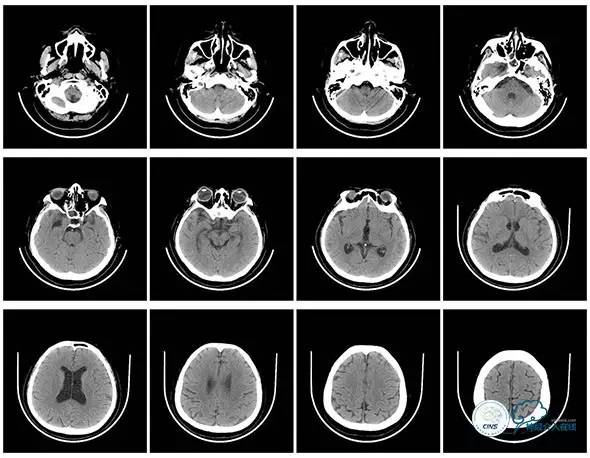

头颅CT

头颅CT(2017.6.20)

颞骨CT(2017.6.20)

2016-06-03 CT

2017-06-07 CT

术后头颅CT